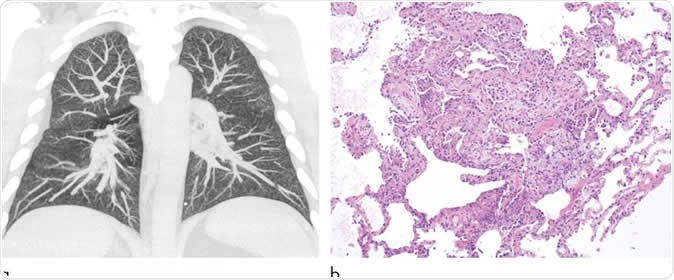

Images show electronic cigarette or vaping product use-associated lung injury in a 32-year-old man with history of vaping who presented with fevers and night sweats for 1 week. (a) Coronal maximum intensity projection image shows diffuse centrilobular nodularity. (b) Histologic sections of his transbronchial cryobiopsy showed distinctive micronodular pattern of airway-centered organizing pneumonia, corresponding to centrilobular nodularity seen at CT. Similar imaging and pathologic findings have been described in patients with smoke synthetic cannabinoids. Image Credit: Radiological Society of North America